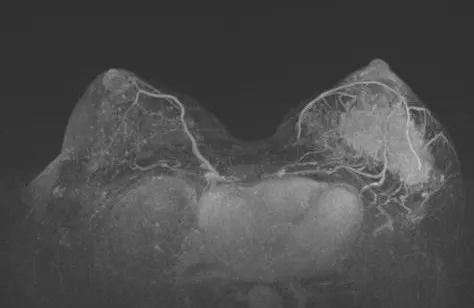

2021-11 乳腺MRI:左乳上份、外上象限见一不规则等T1,等-稍长T2信号肿块,大小约8.2cm×3.7cm×6.5cm,ADC值最低处0.71×10E-3mm2/s,动态增强扫描不均匀显著强化。左腋下多枚肿大淋巴结,大者约2.2cm×1.3cm,增强明显不均匀强化。形状呈不规则,边界欠清楚。

图2. 新辅助治疗前乳腺MRI